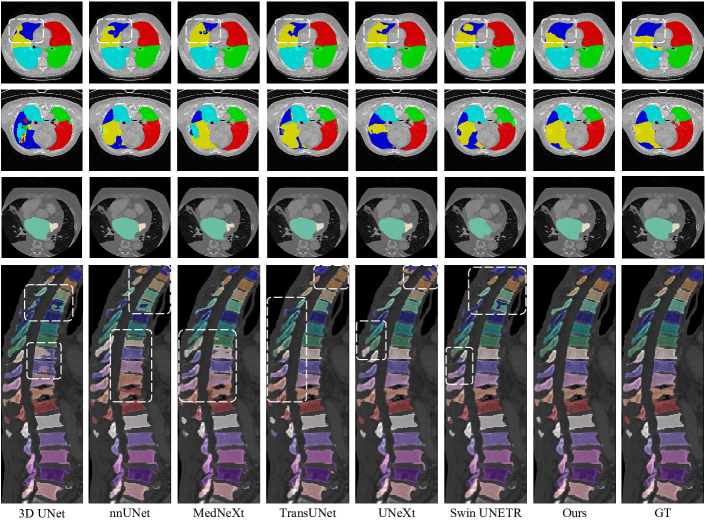

Evaluations on Fused Lung Lobe. To further assess the ability of our model to address boundary confusion, we carried out experiments on the fused lung lobe dataset. Lung lobe CT scans with COVID-19 infections bear uncertain boundaries with noise adjacent to them, which brings a huge challenge for the precise segmentation of inter-class boundaries. Besides, lung lobe CT datasets with COVID-19 infections show a different domain distribution from that of clean lung lobe datasets. Thus, it is more difficult to train a model to implement the segmentation task for the fused lung lobe. Table 2 illustrates the performance comparison between our model and other CNNs and Transformer-based models. We can discover that 3D UNet shows poor segmentation results for the fused lung lobe dataset, which results from the fact that the vanilla structure falls lack of strong representation abilities [87]. Detailedly, Figure 6 reveals that 3D UNet cannot finely localize the boundaries between different parts of lobes. Compared with that, MedNeXt [55] and nnUNet [1] can generate rich voxel-wise features to boost models’ generalization abilities on this multi-domain dataset. Specifically, MedNeXt achieves a Dice score of , a HD95 metric of 7.25mm, an ASSD metric of 1.517mm. As the recent SOTA model, MedNeXt outperforms other models on segmentation metrics for left lobes. However, for right lobes which have a more complicated structure especially on the inter-class boundaries, networks including nnUNet, 3D UX-Net, and Swin UNETR cannot well address the boundary confusion problem. By introducing the pushing and pulling branch into the baseline model, we achieve a Dice increase, 0.69mm HD95 decrease, and 0.200mm ASSD decrease compared with MedNeXt. And it is worth mentioning that PnPNet improves a lot on the metrics for right lobes, with a Dice increase, 2.14mm HD95 decrease, and 0.445mm ASSD decrease. For the right middle lobe with a larger shape variance, our model outperforms nnUNet with a Dice increase, 3.15mm HD95 decrease, and 0.645mm ASSD decrease.

Evaluations on VerSe 2019. We also evaluate the proposed PnPNet on the hidden test dataset of VerSe 2019. As shown in Figure 6, deep segmentation models suffer from the challenge that adjacent vertebrae are not precisely separated by two boundary interfaces. As a result, there is a segmentation inconsistency inside vertebrae. In our model, the pulling branch focuses on squeezing each vertebral region, and is aimed at addressing the challenge of segmentation inconsistency. Besides, the pushing branch helps to precisely localize the boundary region between two adjoining vertebrae. Table 4 shows that PnPNet achieves the best performance on the cervical, thoracic, and average metrics, with a , , and Dice increase respectively. Besides, different CT scans have different field-of-views (FoVs), which makes it difficult for models to identify the last several lumbar vertebrae (Label ). And nnUNet is superior to other models on the ability to localize and segment lumbar vertebrae. Figure 6 demonstrates that PnPNet gives the best visualization results among all models, in which 3D UNet and UNeXt exhibit inconsistent predictions, TransUNet even gives continuous wrong predictions for the label of vertebrae.

Evaluations on LA/LAA. To further validate the effectiveness and robustness of PnPNet, we conduct experiments on the LA/LAA dataset, which is deficient in the uniform standard for annotations of uncertain boundaries. According to Table 4, our model achieves the highest average Dice score of and the lowest average HD95 value of 3.46mm. And the standard deviation of these two metrics is also lower than that of other models, which reveals that PnPNet can improve the segmentation results of the whole dataset to some degree. Here the structure of the left atrial appendage bears various anatomical shapes. Thus, the delineation of the LAA is challenging. Our model surpasses MedNeXt on the Dice score of the LAA with a increase and a smaller standard deviation value.